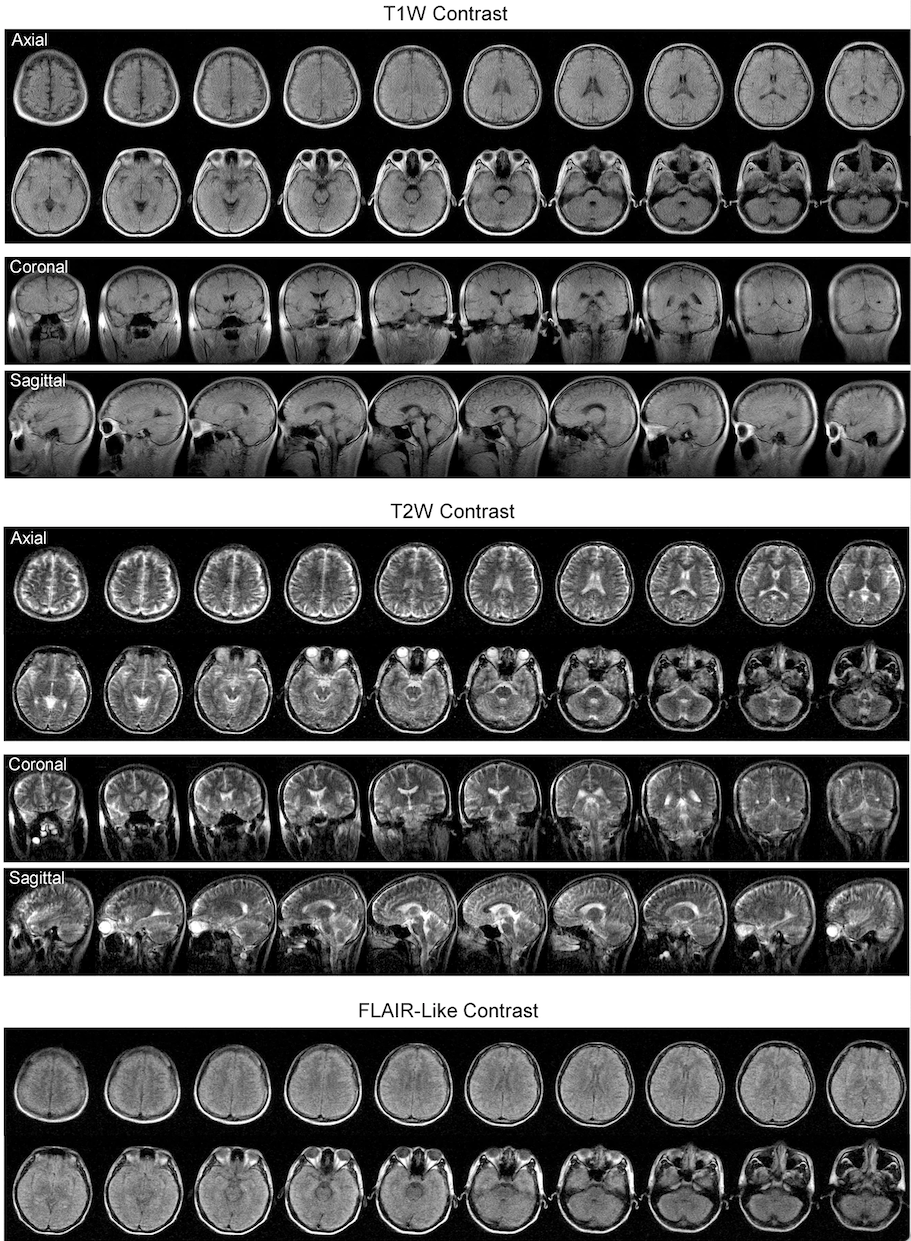

圖為利用超低磁場(ULF)0.055特斯拉腦部磁力共振影像掃描儀拍攝的人腦影像。

據了解,吳學奎團隊與瑪麗醫院神經外科教授梁嘉傑和其他醫生合作,透過將ULF磁力共振影像掃描儀與標準 3 特斯拉磁力共振影像掃描儀獲得的影像進行比較,成功驗證使用 ULF磁力共振影像掃描儀得出的結果。儘管影像清晰度和解像度不及精確診斷所要求程度,他們已能區別出大部分相同病理,包括中風和腫瘤結果。